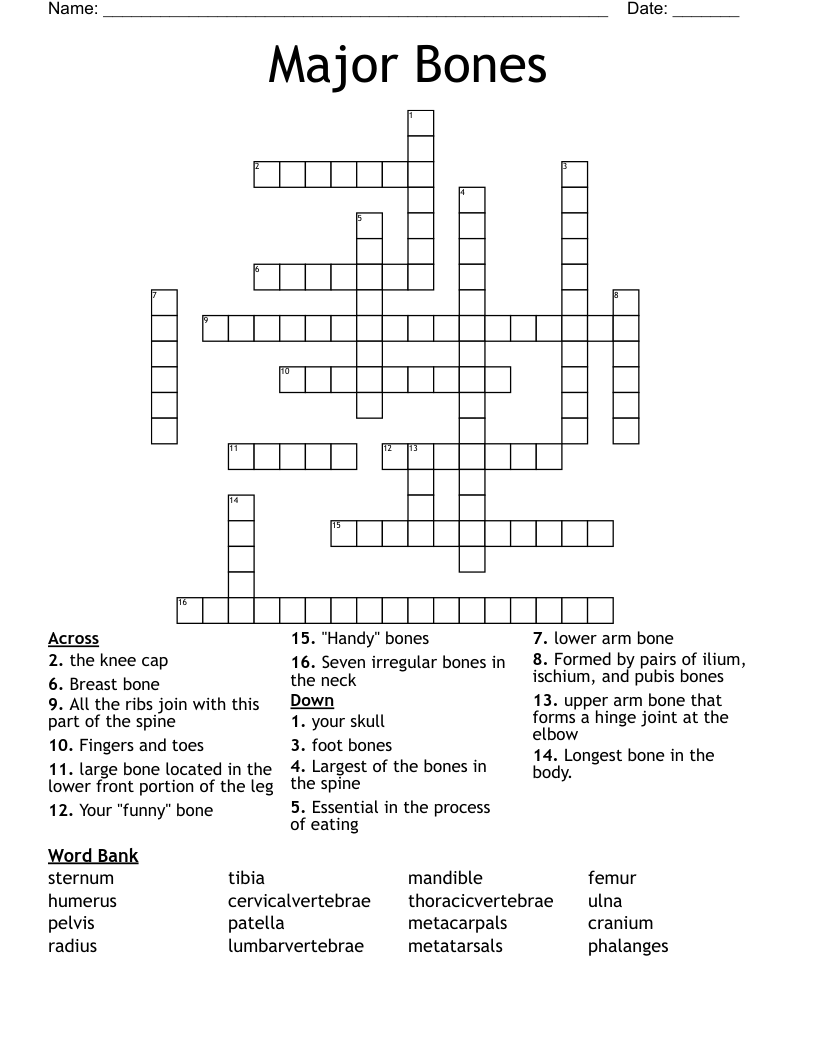

Major Bones Crossword WordMint